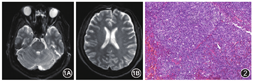

患者男,59岁,因"发作性意识障碍7 h"于2019年4月10日入北京协和医院急诊。患者当日无诱因突发意识障碍,被发现时跌倒在地、言语不清、向右侧凝视,无抽搐、二便失禁,遂就诊于我院。测血压166/86mmHg(1 mmHg=0.133 kPa),其他生命体征基本平稳,浅昏迷状态,躁动,有呻吟,不能言语,查体不合作,双侧病理征阳性,余心肺腹查体无特殊;血常规、血氨、动脉血气分析、肝肾功能、心肌酶、血糖、血电解质、甲状腺功能、抗核抗体谱、抗磷脂抗体谱、狼疮抗凝物、补体、免疫球蛋白、抗人球蛋白试验、系统性血管炎相关抗体等检查均大致正常,完善头颅核磁共振成像检查(MRI)平扫未见异常信号(图1);头颈计算机断层扫描血管造影(CTA)胸腹盆CT平扫均未见异常;完善腰穿,压力155 mmH2O(1 mmH2O=0.0098 kPa);脑脊液常规:细胞数6个/μl(均为单核细胞),脑脊液生化:蛋白1.02 g/L,余指标大致正常;脑脊液病原学:细菌、真菌、奴卡菌、淋球菌涂片,抗酸、墨汁染色、单纯疱疹病毒抗体、乙型脑炎相关抗体、抗接触蛋白相关蛋白-2抗体、抗富含亮氨酸的神经胶质瘤失活蛋白-1抗体、抗N-甲基-D-天冬氨酸受体抗体、抗γ氨基丁酸-B受体2抗体、抗谷氨酸脱氢酶65抗体、抗神经元电压门控钾通道复合体抗体、抗Hu、Yo、Ri抗体等检查均未见异常;查脑电图:前部导联可见较多低波幅4~7 c/s慢波及慢波活动,轻度异常;脑干听觉诱发电位、体感诱发电位未见异常;考虑免疫脑炎可能,予静脉注射用人免疫球蛋白(IVIG)20 g、1次/d、5 d;因躁动予丙泊酚、右美托咪定镇静,后患者意识逐渐恢复,可正常对答,反应稍迟钝,计算力稍差,因患者意识状态进一步好转,患者离院定期神经科门诊随诊,仅口服B族维生素治疗。出院后家属发现患者情绪易怒,有记忆力下降,尤其近期记忆差,常有找词困难、言语不流利、行走稍不稳、步态较前改变,但尚不影响日常生活。5月中下旬曾有劳累后双手抖动,伴头晕,持续数分钟稍缓解,无意识丧失,复查头颅MRI仍未见异常。患者6月4日晚餐后散步时出现站立不稳,于家门前再发意识障碍,伴肢体僵硬,持续约1 min后自行缓解,不伴二便失禁等,但对前述过程不能回忆,故再次入住我院。患者病后食欲、睡眠差,5月下旬加用艾司唑仑助眠后日间睡眠增多,夜间睡眠稍改善。体重近2个月下降5 kg。患者既往体健,有长期大量吸烟史,否认酗酒史,婚育史及家族史无殊。

入院查体:血压90/64 mmHg,心率88次/min,动脉指氧饱和度(SpO2)96%(未吸氧),右侧颈后区可及直径约1.5 cm淋巴结,质韧,活动度可,无明显压痛,余周身浅表淋巴结无肿大。双肺、心脏及腹部查体大致正常;高级智能粗测下降,言语对答部分切题,理解力、定向力差,淡漠,词不达意。四肢肌力肌张力大致正常,双侧掌颌反射、双下肢病理征(+),双手轻微姿势性震颤,行走步基宽,直线行走不能,指鼻、跟膝胫试验欠稳准。入院后完善检查:其中血常规、血涂片、尿常规、肝肾功、叶酸、维生素B12、乳酸脱氢酶(LDH)、肿瘤标记物、抗核抗体谱、系统性血管炎相关自身抗体谱、巨细胞病毒DNA、EB病毒DNA均未见明显异常;完善头颅增强MRI未见异常。结合临床,考虑副肿瘤综合征不能除外,行正电子计算机断层显像(PET-CT),可见右侧咽旁间隙、双颈Ⅰ、Ⅱ、Ⅲ、Ⅳ、Ⅴ区、双侧锁骨上区、双侧腋下、右侧胸大、小肌深面、肝门区、双侧髂血管旁及双侧腹股沟多发代谢增高结节,最高标准摄取值(SUV)为5.5;双侧大脑皮层弥漫性不均匀代谢减低;双侧颞叶内侧皮层代谢相对轻度增高。完善右侧颈部淋巴结活检术,病理回报:(右侧颈部Ⅴ区淋巴结)套细胞淋巴瘤;免疫组化结果:Bcl-2(+),SOX11(+),Bcl-6(-),CD3(散在+),CD5(+),CD10(-),CD20(++),CD23(-),Cyclin D1(+),Ki-67(index 20%),CD30(-),CD15(散在+),C-MYC(-),Mum-1(-),PAX-5(+)(图2)。完善骨髓穿刺,涂片见异常淋巴细胞占4.5%,骨髓流式细胞免疫分型可见异常表型B细胞,占样本中非红细胞比例为17.8%,主要表达CD19、CD5、CD22、CD20、CD11c、CD25,不表达CD23、CD138、CD38、CD10、CD103、CD34等;复查腰椎穿刺,脑脊液压力150 mmH2O,脑脊液蛋白1.17 g/L,白细胞介素(IL)-6、IL-10水平正常,脑脊液流式细胞免疫分型未见异常细胞。考虑套细胞淋巴瘤诊断明确,因患者多次复查头部影像学均未见异常病灶,且脑脊液中未见异常细胞,故考虑神经系统病变系副肿瘤综合征所致,而非中枢神经系统受累。分期方面,患者存在周身淋巴结及骨髓受累,病程中有发热及消瘦情况,分期为ⅣB期;同时因患者年龄<60岁,LDH正常,美国东部肿瘤协作组(ECOG)评分1分,故国际预后指数(IPI)评分1分,因患者白细胞计数<6.7×109/L,MCL国际预后指数(MIPI)1分,为低危组。患者转入血液科进一步治疗,应用R-DHAP(美罗华、顺铂、阿糖胞苷、地塞米松)及R-CHOP(美罗华、环磷酰胺、表柔比星、长春地辛、泼尼松)方案交替化疗治疗,并鞘内注射地塞米松5 mg+阿糖胞苷50 mg。目前已完成5程化疗,化疗后复查腰穿检查:测量脑脊液压力波动于150 mmH2O左右,脑脊液蛋白逐渐下降,目前为0.53 g/L,测量脑脊液IL-6及IL-10均在正常范围内。患者1程化疗后意识状态逐步好转,情绪稳定,记忆力、定向力逐渐恢复至正常,并可进行正常工作。4程化疗后复查PET-CT示:原有代谢增高淋巴结均基本消失,仅见双侧颈部、左侧锁骨上及双侧腹股沟散在小淋巴结,代谢无明显异常,双侧大脑皮层弥漫性不均匀代谢减低;双侧颞叶内侧皮层代谢相对轻度增高情况同前;复查头颅增强MRI仍未见明显异常信号。目前仍继续化疗中。